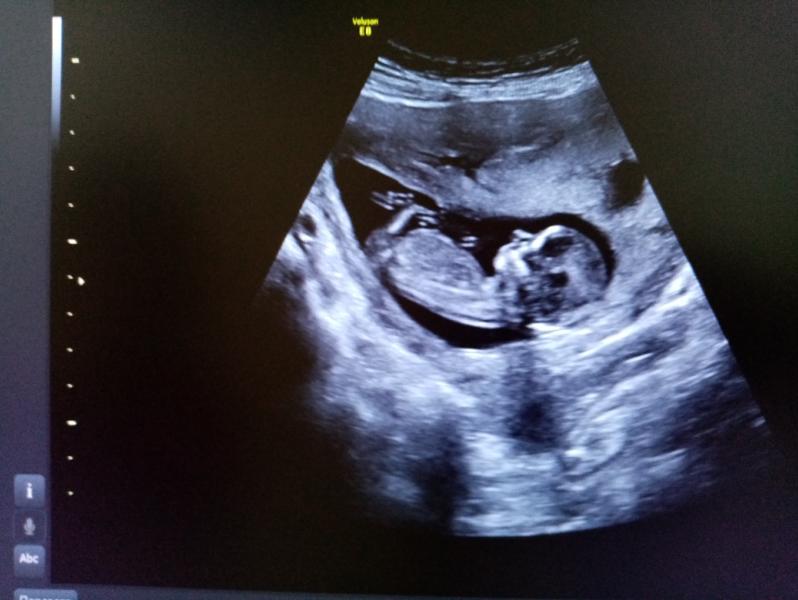

На УЗИ нам 12 недель 😇 А на фото с пузиком 20 недель 🥰